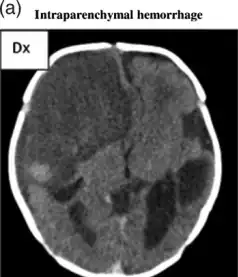

| File:Multiple intraparenchymal hemorrhage.jpg | |

| Multiple intraparenchymal hemorrhage | |

CT scan shows a very large intraparenchymal haemorrhage with mass effect and occupying most of the right frontal lobe

Computed tomography (CT scan): A CT scan may be normal if it is done soon after the onset of symptoms. A CT scan is the best test to look for bleeding in or around your brain. In some hospitals, a perfusion CT scan may be done to see where the blood is flowing and not flowing in your brain.